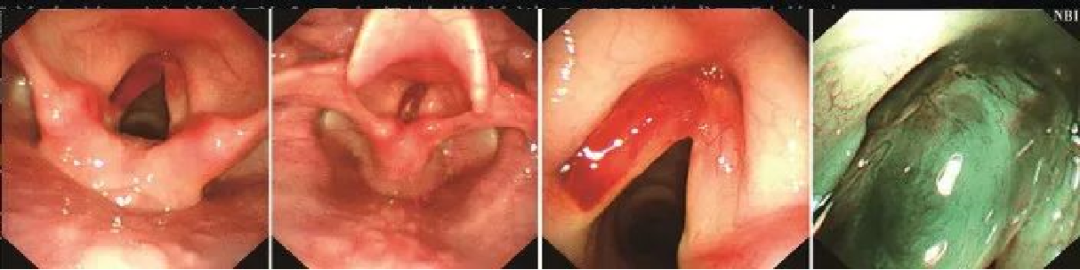

声门型喉癌

为什么喉镜后做活检电子鼻咽喉镜,让鼻、咽、喉部疾病无处可藏——2021橙乡微创论坛精彩速递(五)_https://www.jmylbn.com_新闻资讯_第17张

A.外院喉镜检查发现右侧声带中部白斑,未取活检,性质难定;

B、C.声门区右侧声带中部可见白斑(活检4块),白斑周围黏膜充血;

D.NBI模式下可见白斑周围充血处黏膜有明显的斑点状表现。